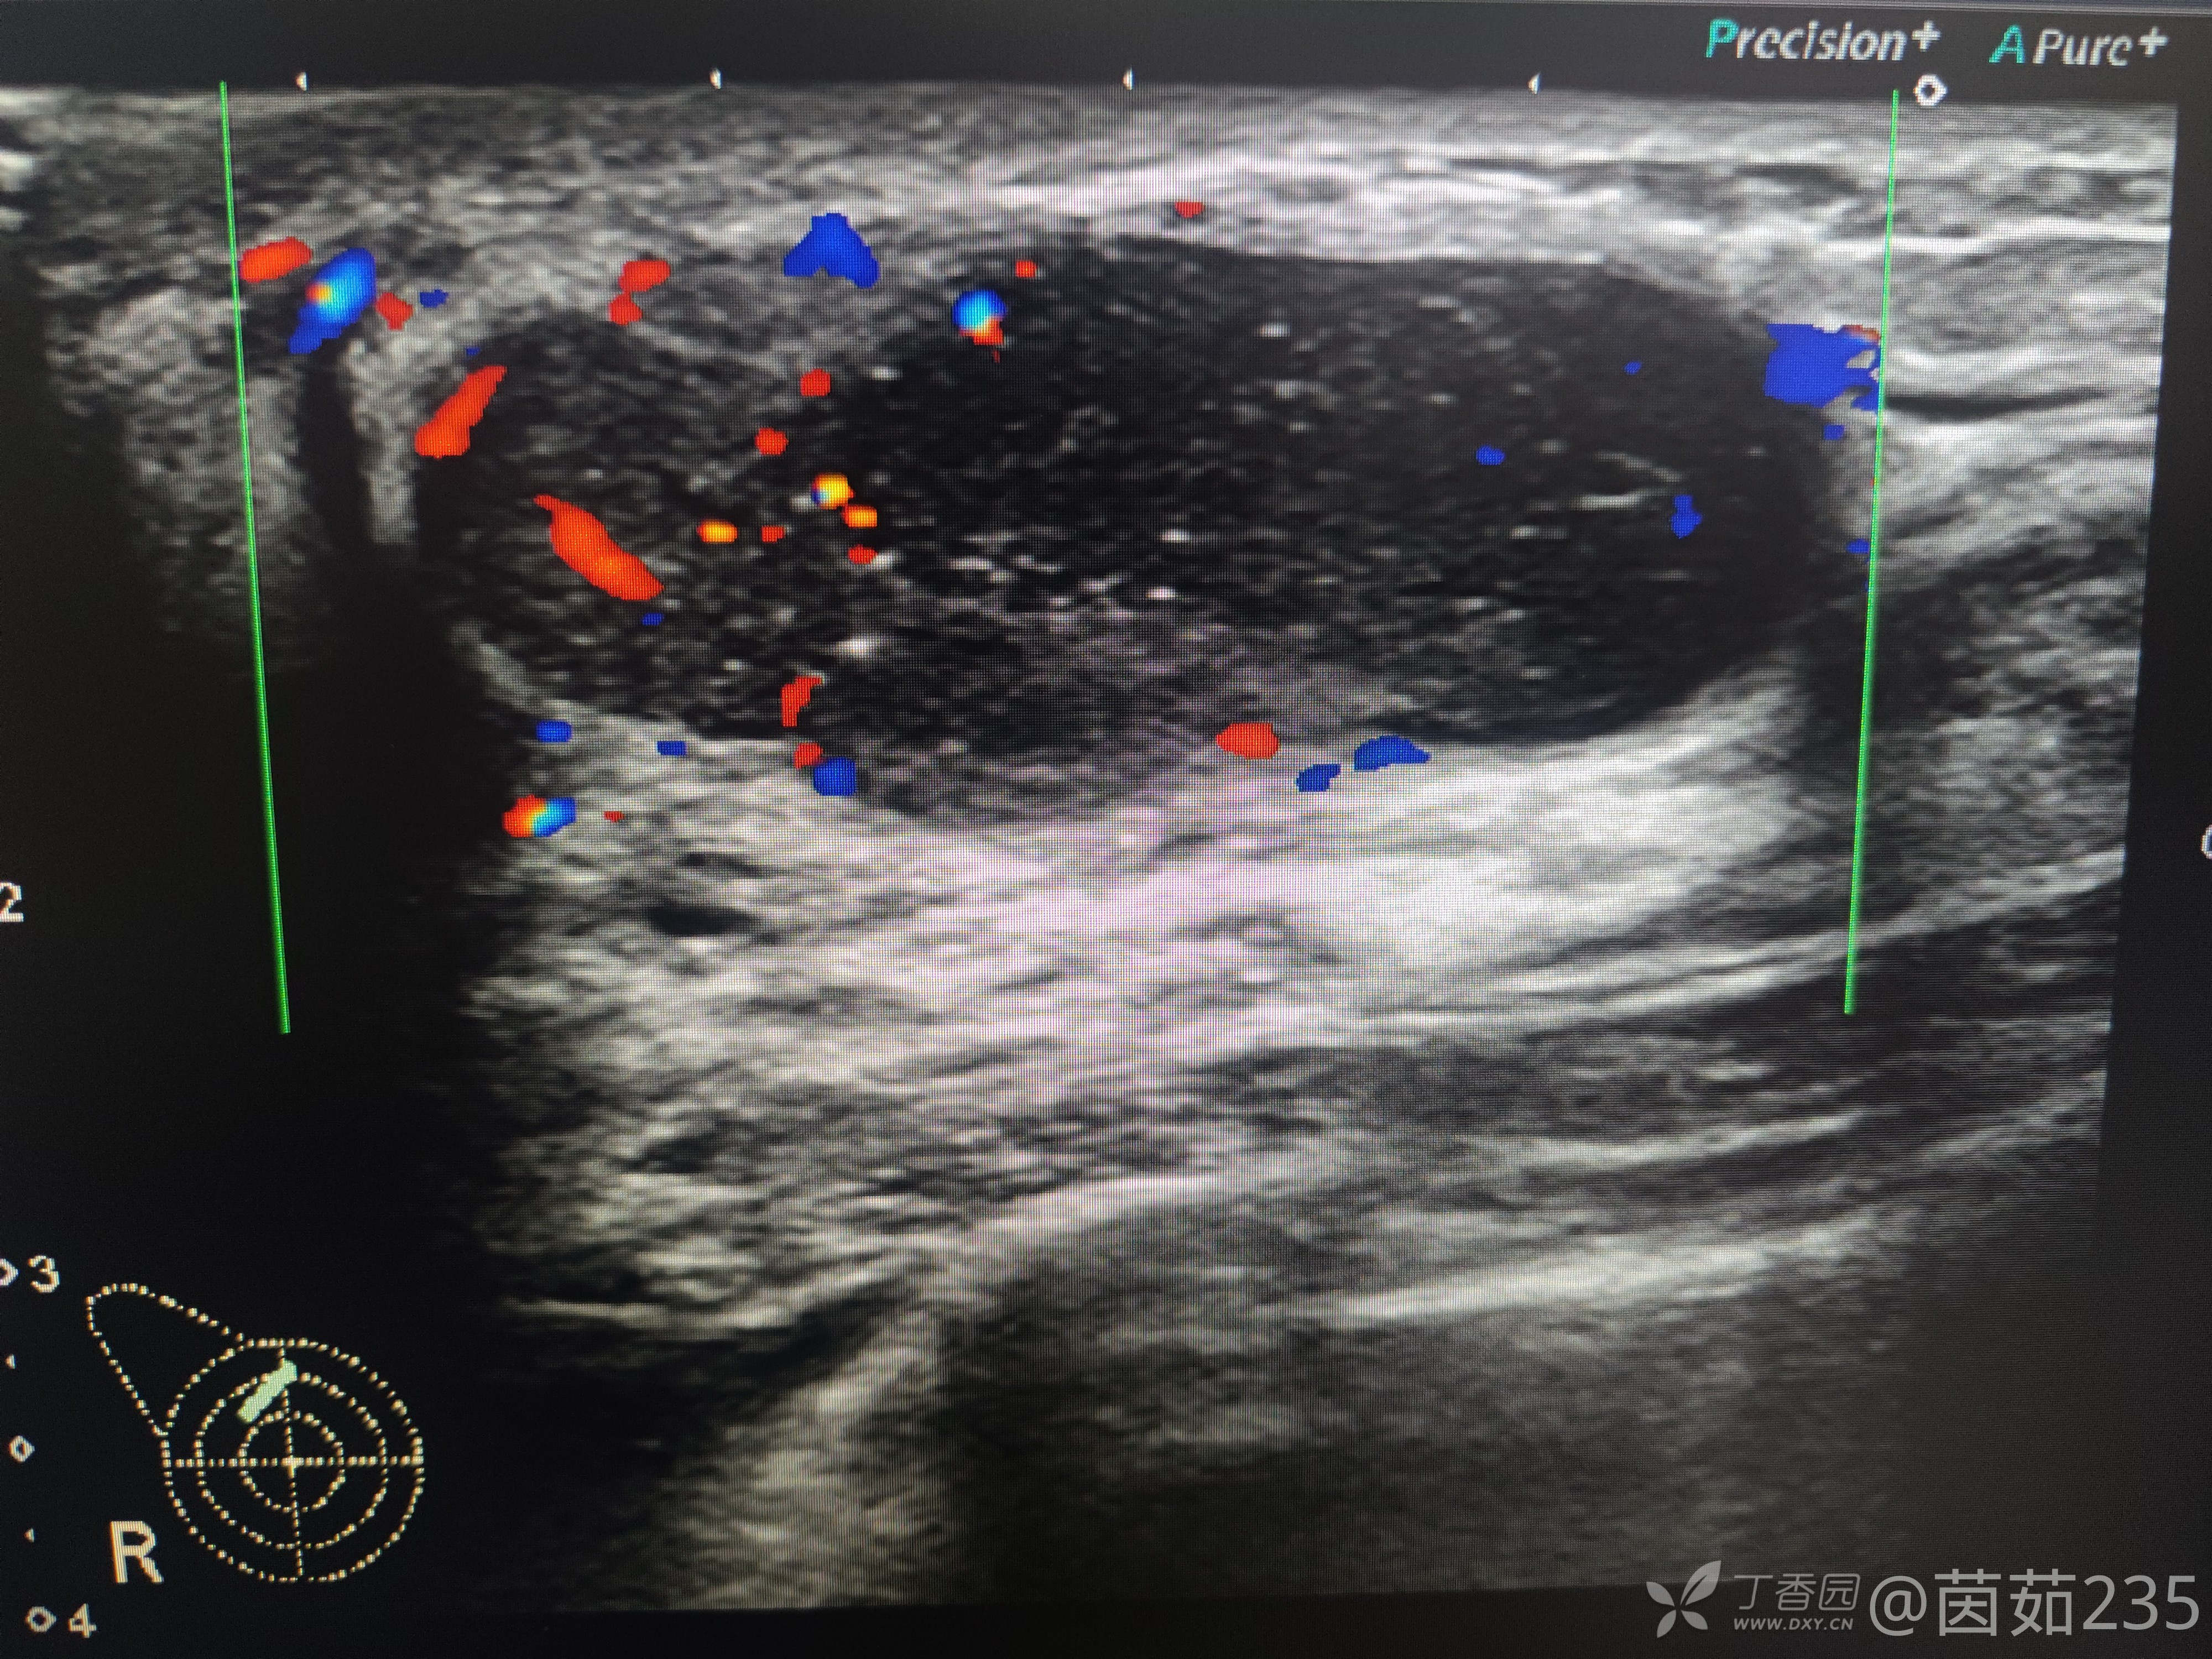

右侧乳腺12点乳晕后方腺体内可见一低回声包块,大小37✖️16mm,边界清,壁厚,内回声不均,可见数个彗星尾。来看看图,你们觉得该分几类?考虑是什么?